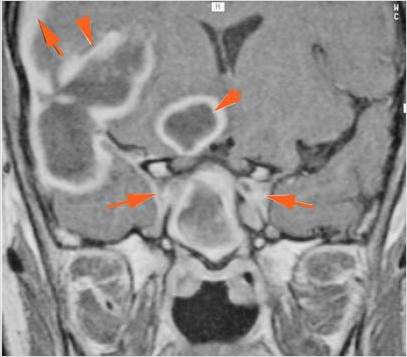

Intracranial

There is a subperiosteal fluid collection or abscess along the boney walls of the anterior or middle cranial fossa. [Yes/No]

There is an epidural fluid collection or abscess along the boney walls of the anterior or middle cranial fossa. [Yes/No]

There is a subdural fluid collection or abscess along the boney walls of the anterior or middle cranial fossa. [Yes/No]

There is a subdural fluid collection or abscess along the falx cerebri or within the tentorium. [Yes/No]

There is evidence of thrombus, thrombophlebitis or other occlusive or inflammatory process of the cortical veins, sphenoparietal sinus or sagittal sinus. [Yes/No]

There is evidence of thrombus, thrombophlebitis or other occlusive or inflammatory process of the cavernous sinus. [Yes/No]

There is evidence of inflammation of the distal internal carotid artery. [Yes/No]

There is evidence of an infectious aneurysm. [Yes/No]

There is brain edema specifically involving the frontal and temporal lobes. [Yes/No]

There is cerebritis specifically involving the frontal and temporal lobes. [Yes/No]

There is brain abscess specifically involving the frontal and temporal lobes. [Yes/No]

There is likely meningitis, meningoencephalitis with complicating hydrocephalus or brain herniation. [Yes/No]